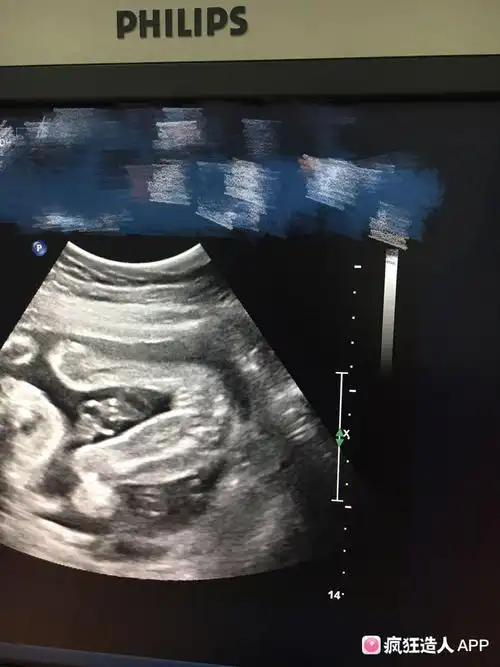

男宝宝和女宝宝的生理特征大不相同,女孩是明显的三条线标志,男孩是

二维彩超报告三条线看胎儿是男是女的方法准吗

宝妈,看看我这个是男孩女孩啊!感觉是两个亮点,又像是三条线

nt三个亮点是男孩女孩男孩女孩生殖特征点区别

nt图有三条线是女孩怀孕12周nt图女孩的标志

有没有能够确认怀的是男宝的b超三条线图片